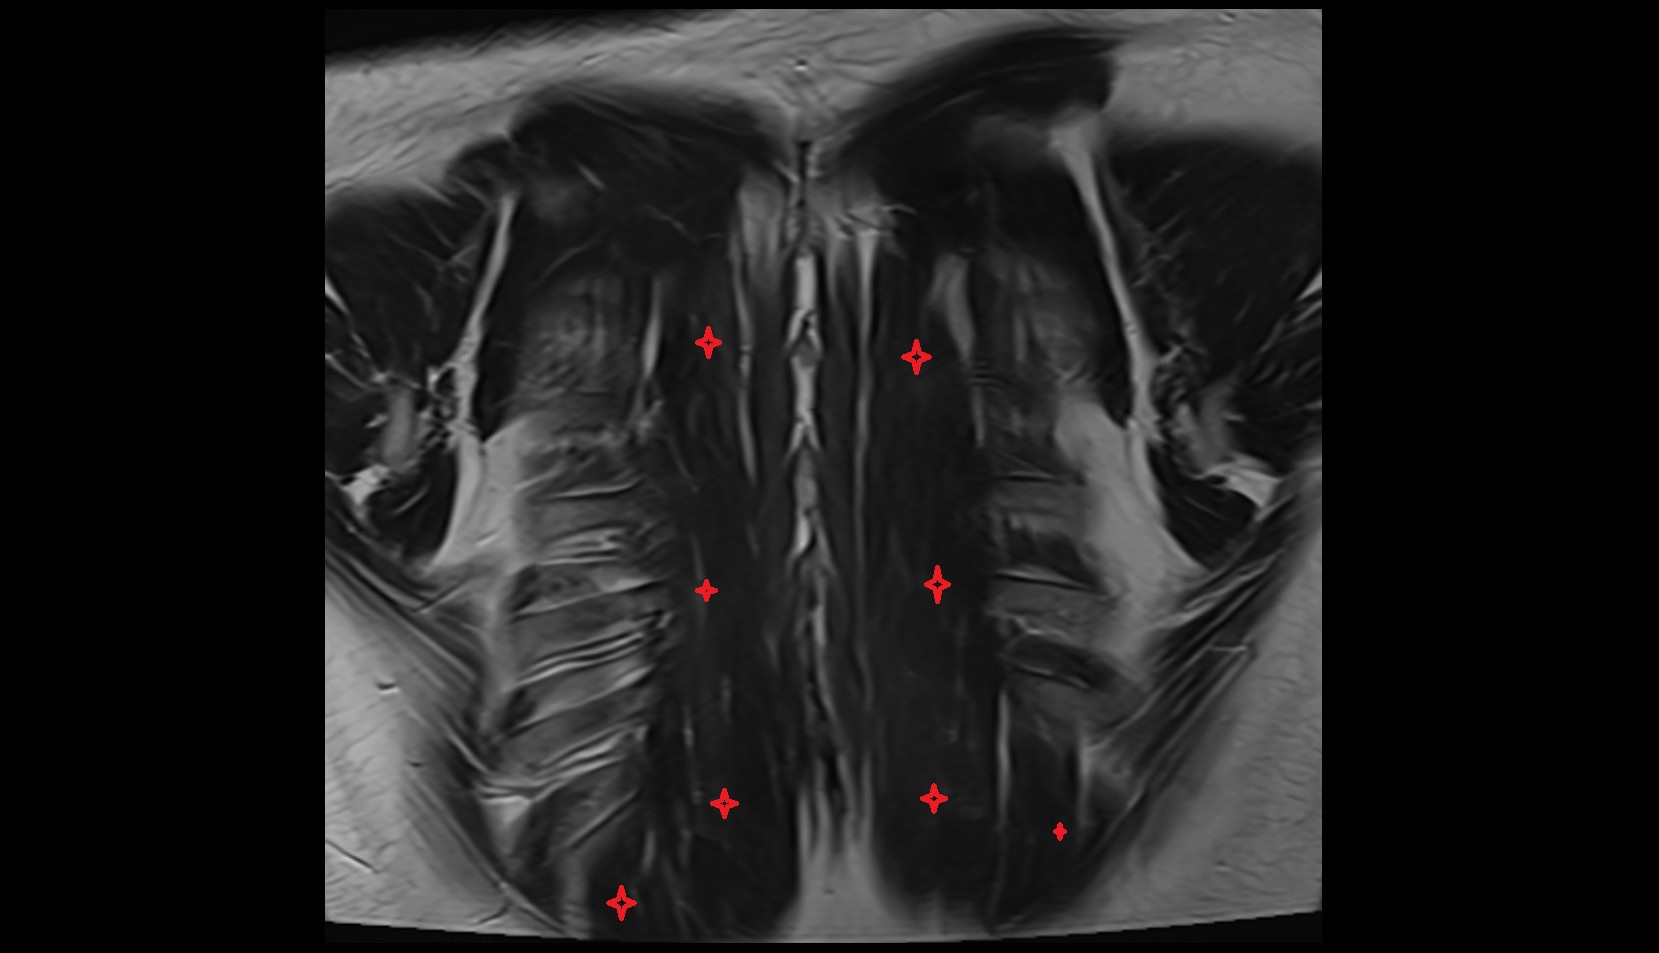

- Exiting nerve root of spinal nerve S1

- Traversing nerve root of spinal nerve S1

- Traversing nerve root of spinal nerve S2

- Traversing nerve root of spinal nerve S3

- Traversing nerve root of spinal nerve S4

- Exiting nerve root of spinal nerve S2

- Exiting nerve root of spinal nerve S3

- Exiting nerve root of spinal nerve S4

- Exiting nerve root of spinal nerve S5